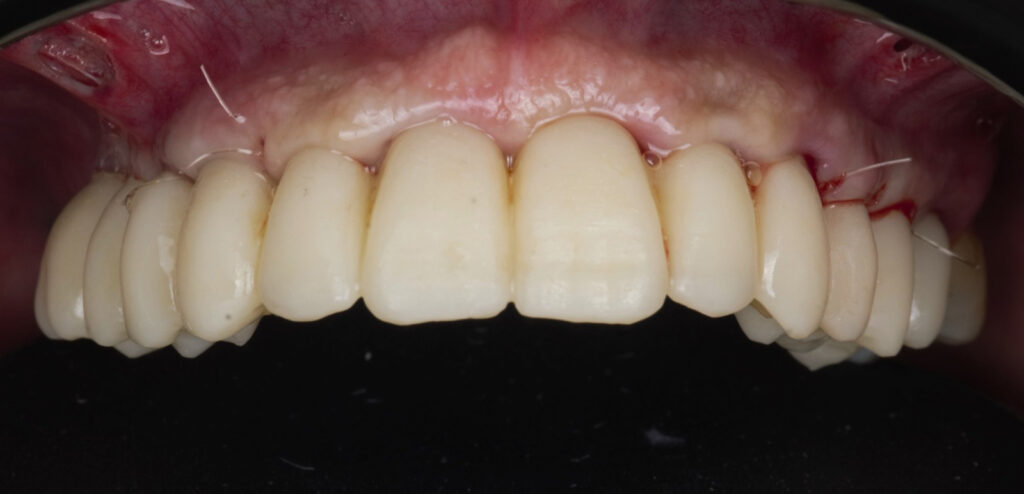

Caso clínico, Dr. José Amador Cabezas

Carga inmediata maxilar con cirugía guiada, registro fotogramétrico y provisionalización inmediata.

En este caso, el Dr. José Amador Cabezas aborda la rehabilitación completa de un maxilar superior comprometido por enfermedad periodontal avanzada, lesiones periapicales y múltiples restauraciones fallidas.

Tras la planificación protésicamente guiada y la colocación de implantes mediante cirugía guiada, se realizó el registro fotogramétrico con T-Marker sobre los Multi-Unit para capturar con precisión la posición real de los implantes y asegurar la pasividad de la estructura provisional.

Gracias a este flujo, el paciente pudo salir de la consulta con una prótesis fija inmediata el mismo día de la cirugía, iniciando así un proceso restaurador más preciso, más predecible y completamente integrado en el entorno digital.

La combinación de cirugía guiada, fotogrametría y carga inmediata permite un control preciso de la posición implantaria y una correcta pasividad protésica desde el primer día.